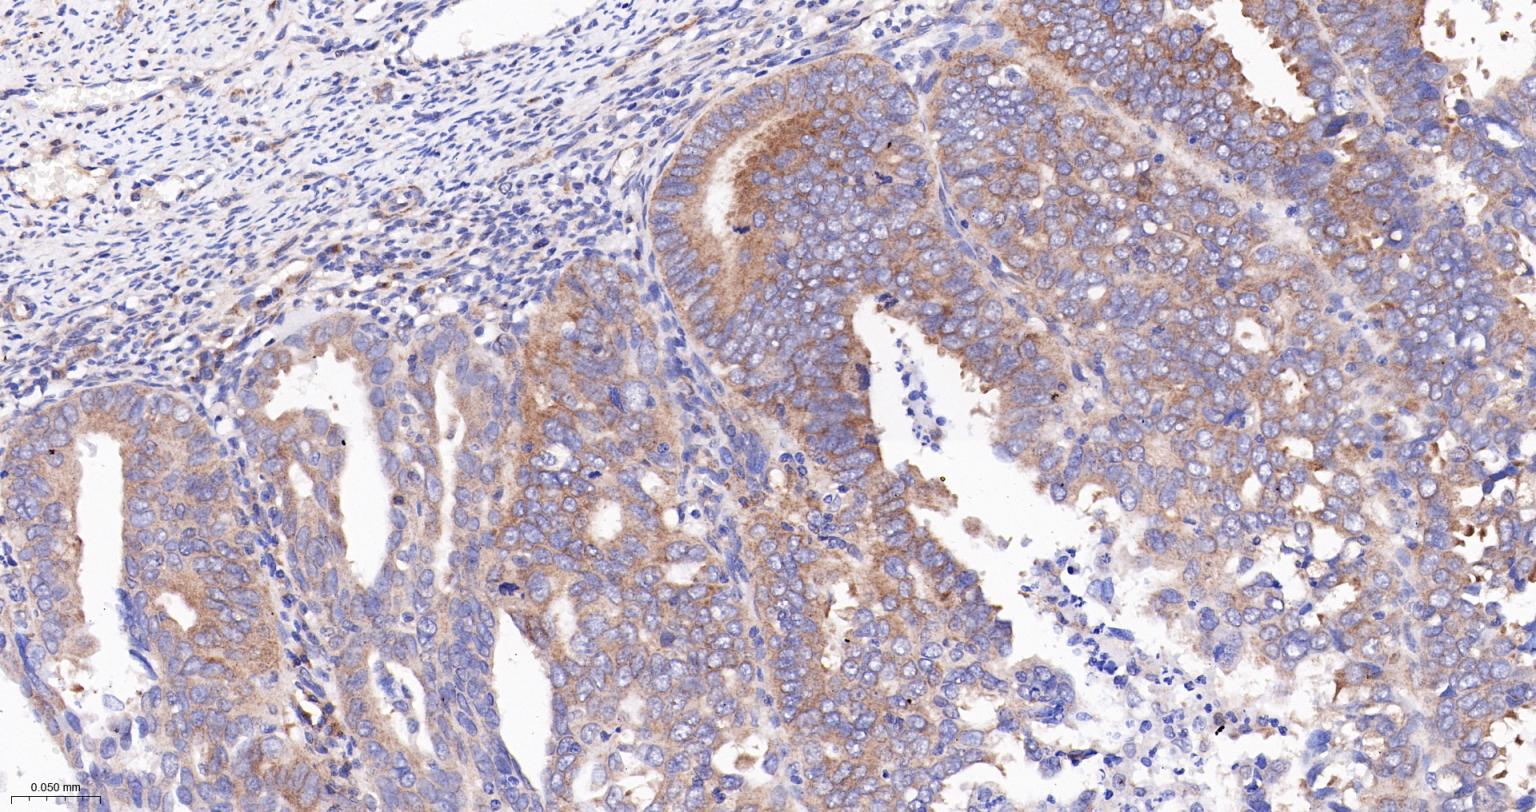

Paraformaldehyde-fixed, paraffin embedded Human Colon Cancer; Antigen retrieval by boiling in sodium citrate buffer (pH6.0) for 15 min; The section was incubated with Exportin 1 Recombinant Monoclonal Antibody, Unconjugated (bsm-61790R) at 1:200 overnight at 4°C, followed by conjugation to the bs-0295G-HRP and DAB (C-0010) staining.